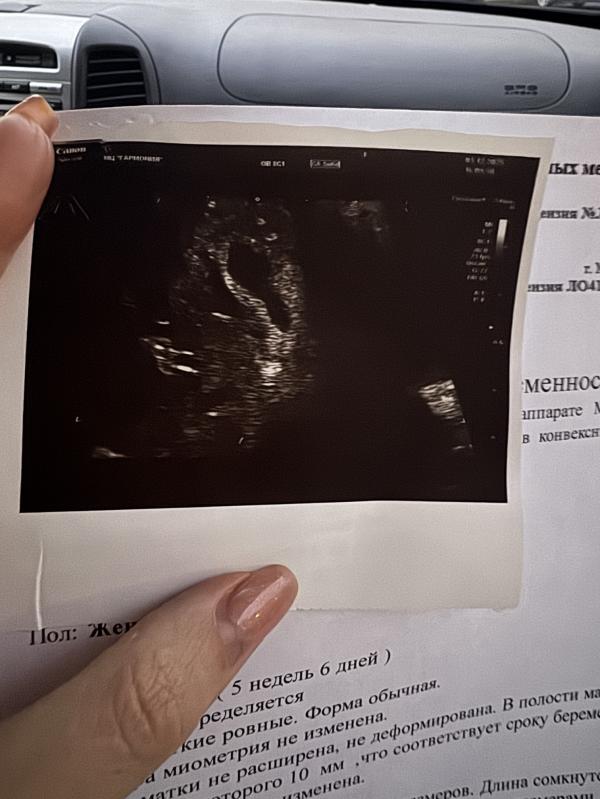

Вы понимаете, что из этого ПЯ, а что отслойка???

Врач так еще сказала: "ПЯ внизу" угрожающе... и деформировано из-за тонуса

Наверно вот что крупное пятно это плодное яйцо